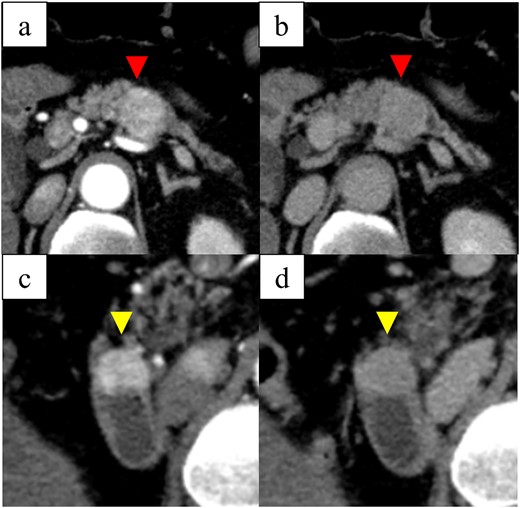

In 2010, a 54-year-old man underwent laparoscopic total right nephrectomy for RCC at our hospital. Renal cell carcinoma was diagnosed. Based on the criteria of the 8th edition of the UICC the tumor was diagnosed as T1aN0M0 Stage I. The patient did not receive adjuvant chemotherapy after the nephrectomy, and was free of recurrence for 12 years after surgery. In March 2022, he was referred to our hospital with a chief complaint of right upper abdominal pain. Enhanced computed tomography (CT) showed an enlarged gallbladder with findings characteristic of acute cholecystitis. CT also revealed 27- and 20-mm hypervascular tumors in the pancreatic body and descending duodenum near the papilla of Vater. The tumors appeared well enhanced in the arterial phase and washed out in the venous phase (Figs 1 and 2).

Computed tomography images: (a) arterial-phase axial computed tomography shows a hypervascular tumor in the pancreatic body, (b) the pancreatic tumor was washed out in the venous phase, (c) arterial-phase axial computed tomography shows a hypervascular tumor in the descending duodenum, and (d) the duodenal tumor was washed out in the venous phase.